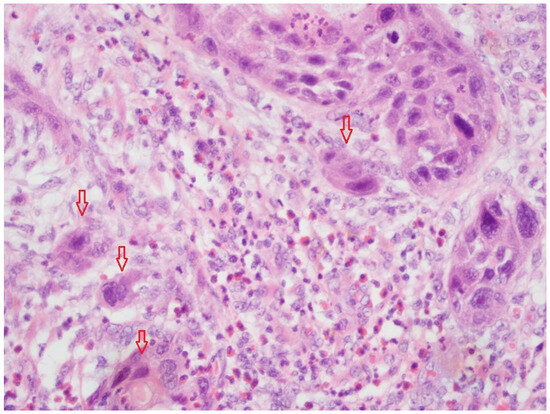

Figure 2 shows TB in a cryo-fixed tissue slide (HE, magnification 20×). The HPF presents a low TB and a TB score of 1.

Figure 2. Example section of cryo-fixed HNSCC tissue (HE, magnification 20×) with tumor budding. The red arrows show the tumor budding nest of the cell (<4 cells/TB). This HPF presents low tumor budding (TB score 1). It is clearly visible that the tissue quality is poorer due to the cryo fixation process, compared with FFPE sections (Figure 1).